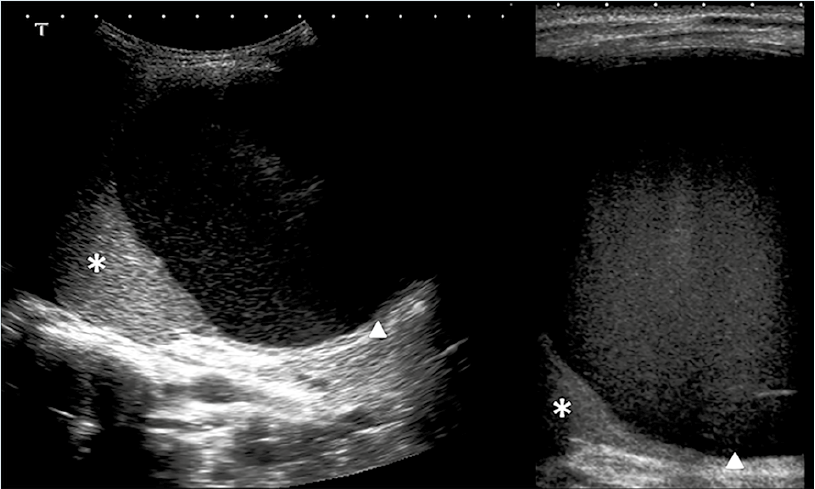

Con el diagnóstico de neumonía basal izquierda se decidió hospitalizarlo para tratamiento antibiótico intravenoso con ampicilina (150 mg/kg/ día) y administración de oxígeno. Al tercer día, por persistencia de los síntomas, se solicitó una ecografía abdominal en la que se observó una lesión quística intraesplénica de gran tamaño (aproximadamente 113 x 103 x 116 mm), hipoecogénica y homogénea (Figura 1). Se realizó una punción-aspiración guiada y se dejó un catéter tipo pigtail en el interior (Figura 2), con mejoría clínica y analítica inmediata.

En el cultivo del absceso creció Salmonella serogrupo D. El drenaje permaneció durante 10 días; los datos clínicos reaparecieron a los 5 días del retiro del catéter, con un nuevo pico febril y aumento de las necesidades de oxígeno

suplementario. Ante la confirmación ecográfica del aumento del tamaño de la colección líquida intraesplénica y hepatización del lóbulo inferior izquierdo pulmonar, se decidió una tomografía computada (Figura 3) para definir la localización exacta de la lesión y su relación con las estructuras vecinas. Se volvió a drenar guiándose con control ecográfico y se programó para capsulectomía definitiva. En la intervención se encontraron una lesión grande encapsulada en la región anterior del bazo, en relación directa con el ligamento gastrocólico y la cúpula vesical, de contenido mixto purulento-sanguinolento. Se efectuaron la extirpación quística parcial y la fenestración de la cápsula. El análisis anato mopatológico de la pieza fue compatible con quiste epitelial primario.